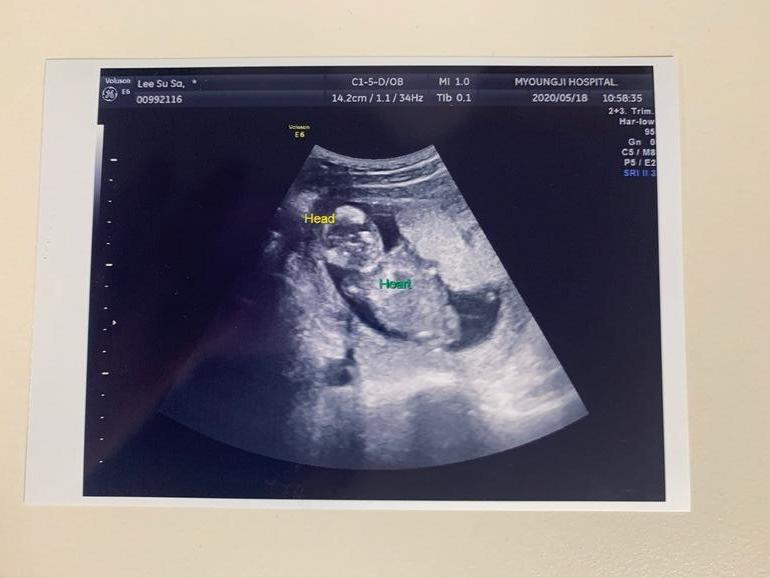

УЗИ, КТГ, доплерВ прошлый раз была у врача ровно в 15 недель. Клинику пока решили не менять, ходим к старому врачу, - он намного опытнее.Тогда всё посмотрели, сказали что норма и отпустили. Наш врач на первом скрининге пол не предполагал, а в 15 недель малыш скрестил ножки, а потом и вовсе отвернулся😌Вчера, поскольку срок 18 и 2 по месячными и 18 и 3 по УЗИ врач сказал сдавать тройной тест. Результаты будут в конце недели, так что остаётся только ждать. По УЗИ всё в норме, но врач говорит, что похоже на девочку. Я даже растерялась как-то, ожидала что подтвердят нам мальчика и начну уже потихоньку что-то выбирать малышу, но наш врач сказал что ничего мальчикового не видит🤷♀️И если раньше мы с мужем больше хотели девочку, то сейчас уже привыкли и полюбили мальчика внутри, над именем думали, а тут...)Придётся ждать ещё 3 недели, видимо. Но это не главное, конечно. Главное, чтобы малыш был здоров🙏Фото УЗИ 15, 18 и 13 недель ( на 13-ой неделе другая клиника)